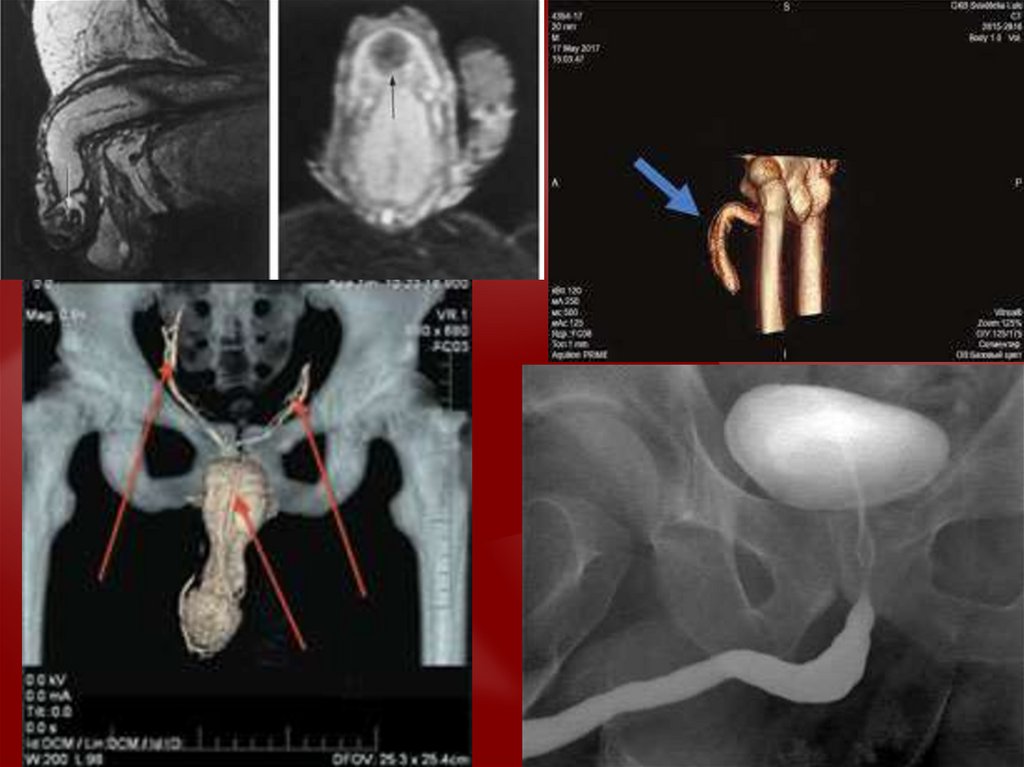

Диагностика травмы половых органов

• Перелом полового члена

• Вывих полового члена

• Ущемление полового члена